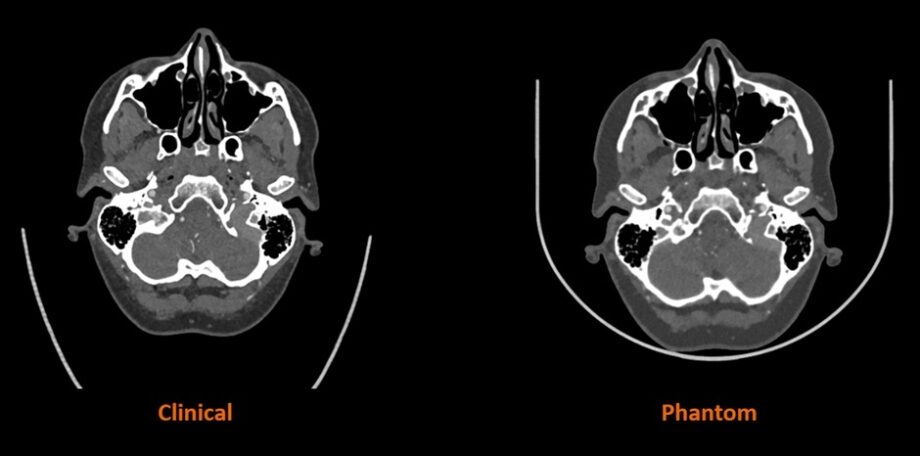

A CT-szkennerek az orvosi képalkotás létfontosságú eszközei és a kórházak szinte univerzális felszerelései világszerte. A CT-fantomok olyan speciális eszközök, amelyeket a CT-szkennerek teljesítményének értékelésére és biztosítására használnak. Az emberi test bizonyos jellemzőinek szimulálására tervezett fantomok lehetővé teszik különböző alapvető mérőszámok, többek között a sugárdózis és a képminőség értékelését, segítve a kalibrációt és biztosítva a szkenner konzisztens teljesítményét. A közös fejlesztés a Stratasys PolyJet™ technológiáját és egyedülálló RadioMatrix™ alapanyagát kombinálja a Siemens Healthineers fejlett algoritmusával, hogy a szkennelt betegképeket konkrét anyagjellemzőkké alakítsa át az emberi anatómia radiológiai tulajdonságainak megfelelően. A megoldás lehetővé teszi a személyre szabott fantom-gyártást és az ultrarealisztikus emberi anatómiai jellemzők létrehozását a betegspecifikus patológia teljes radiológiai pontosságával, ami korábban nem volt lehetséges.

Ez a közös projekt átalakítja a fantomok felhasználásának módját az orvostudományban, és egyes esetekben lehetővé teszi az eszközgyártók és a tudományos intézmények számára, hogy az emberi holttesteket 3D nyomtatott modellekkel helyettesítsék. Ez a megoldás rendkívüli hatékonyságot tesz lehetővé, és minimalizálja az elkerülhetetlen emberi eltéréseket. A munka fontos kutatási adatokat is eredményez majd, amelyek kulcsfontosságú ismereteket nyújtanak a CT-rendszer algoritmusainak fejlesztéséhez, az anyagfejlesztés ösztönzéséhez és a lehetséges új alkalmazási területek feltárásához, valamint a jövőbeli kutatási lehetőségek beazonosításához.

A kutatás a feji és nyaki régió kisebb méretű anatómiáinak 3D nyomtatott fantomjainak gyártásával kezdődik, majd fokozatosan egyre nagyobb és összetettebb anatómiák előállítását célozza meg – egészen az első fázis végpontjáig, a szívmodell és egy teljes emberi törzs 3D nyomtatásáig, teljes röntgenfelvételi pontossággal.